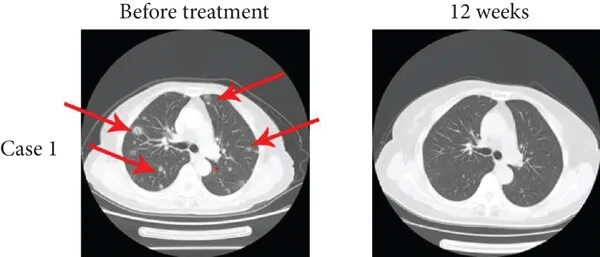

其中1例为一位15岁男性肺转移患者,在接受TIL疗法联合抗PD-1疗法12周后,达到完全缓解(CR),多发性肺转移灶消失(详见下图a),中位无进展生存期(PFS)为15个月。

▲图源“J Immunol Res”,版权归原作者所有,如无意中侵犯了知识产权,请联系我们删除

另一例为20岁男性肝转移患者,经12周TIL联合纳武利尤单抗治疗后,达到完全缓解(CR),肝转移灶消失(详见下图b),中位无进展生存期(PFS)为12.1个月。